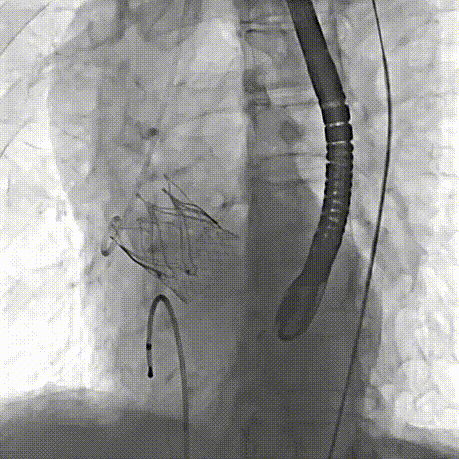

2026年伊始,TaurusTrio经导管主动脉瓣系统在复旦大学附属中山医院,浙江大学医学院附属第二医院,中国医学科学院阜外医院,首都医科大学附属北京安贞医院,四川大学华西医院等多家临床中心成功开展上市后全国首批植入。这不仅是TaurusTrio正式走向广泛临床应用的重要里程碑,更标志着中国单纯主动脉瓣反流介入治疗正式迈入了“心键合璧”的全新纪元。

首植告捷,新程启幕。TaurusTrio的成功获批与全国首批植入的正式启动,不仅是沛嘉医疗深耕结构性心脏病领域、坚持自主创新与临床需求深度融合的重要里程碑,更是我国结构性心脏病介入诊疗领域的关键技术突破。